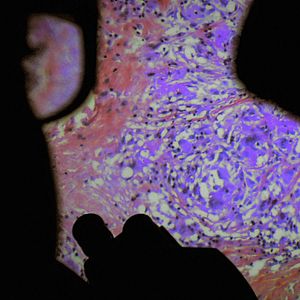

Der menschliche Körper als Konstrukt, betrachtet durch die Linse der Chirurgie: Ein Dokumentarfilm von Véréna Paravel and Lucien Castaing-Taylor, inspiriert von Andreas Vesalius' berühmter Schrift über die menschliche Anatomie "De Humani Corporis Fabrica" (1543).